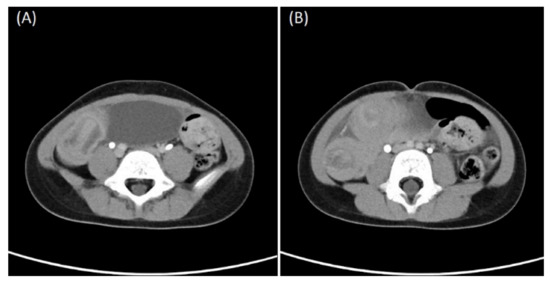

Meckel’s Diverticulum as a Cause of Small Bowel Obstruction Complicated with Gangrene in the Third Trimester of Pregnancy: A Case Report

Acute abdomen during pregnancy is rare. Despite advances in diagnostic imaging, preoperative diagnosis in the pregnant population due to anatomical and physiological changes can pose difficulties. Diagnosis and surgery delays increase the risk of adverse outcomes for both maternal and fetal health. In [...] Read more.

Acute abdomen during pregnancy is rare. Despite advances in diagnostic imaging, preoperative diagnosis in the pregnant population due to anatomical and physiological changes can pose difficulties. Diagnosis and surgery delays increase the risk of adverse outcomes for both maternal and fetal health. In symptomatic cases, explorative surgery might be essential for correct diagnosis and patient treatment. Here, we present Meckel’s diverticulum as an unusual cause of small bowel obstruction complicated with gangrene in a 34-week pregnant patient. The diagnosis was only apparent during explorative surgical laparotomy. Full article